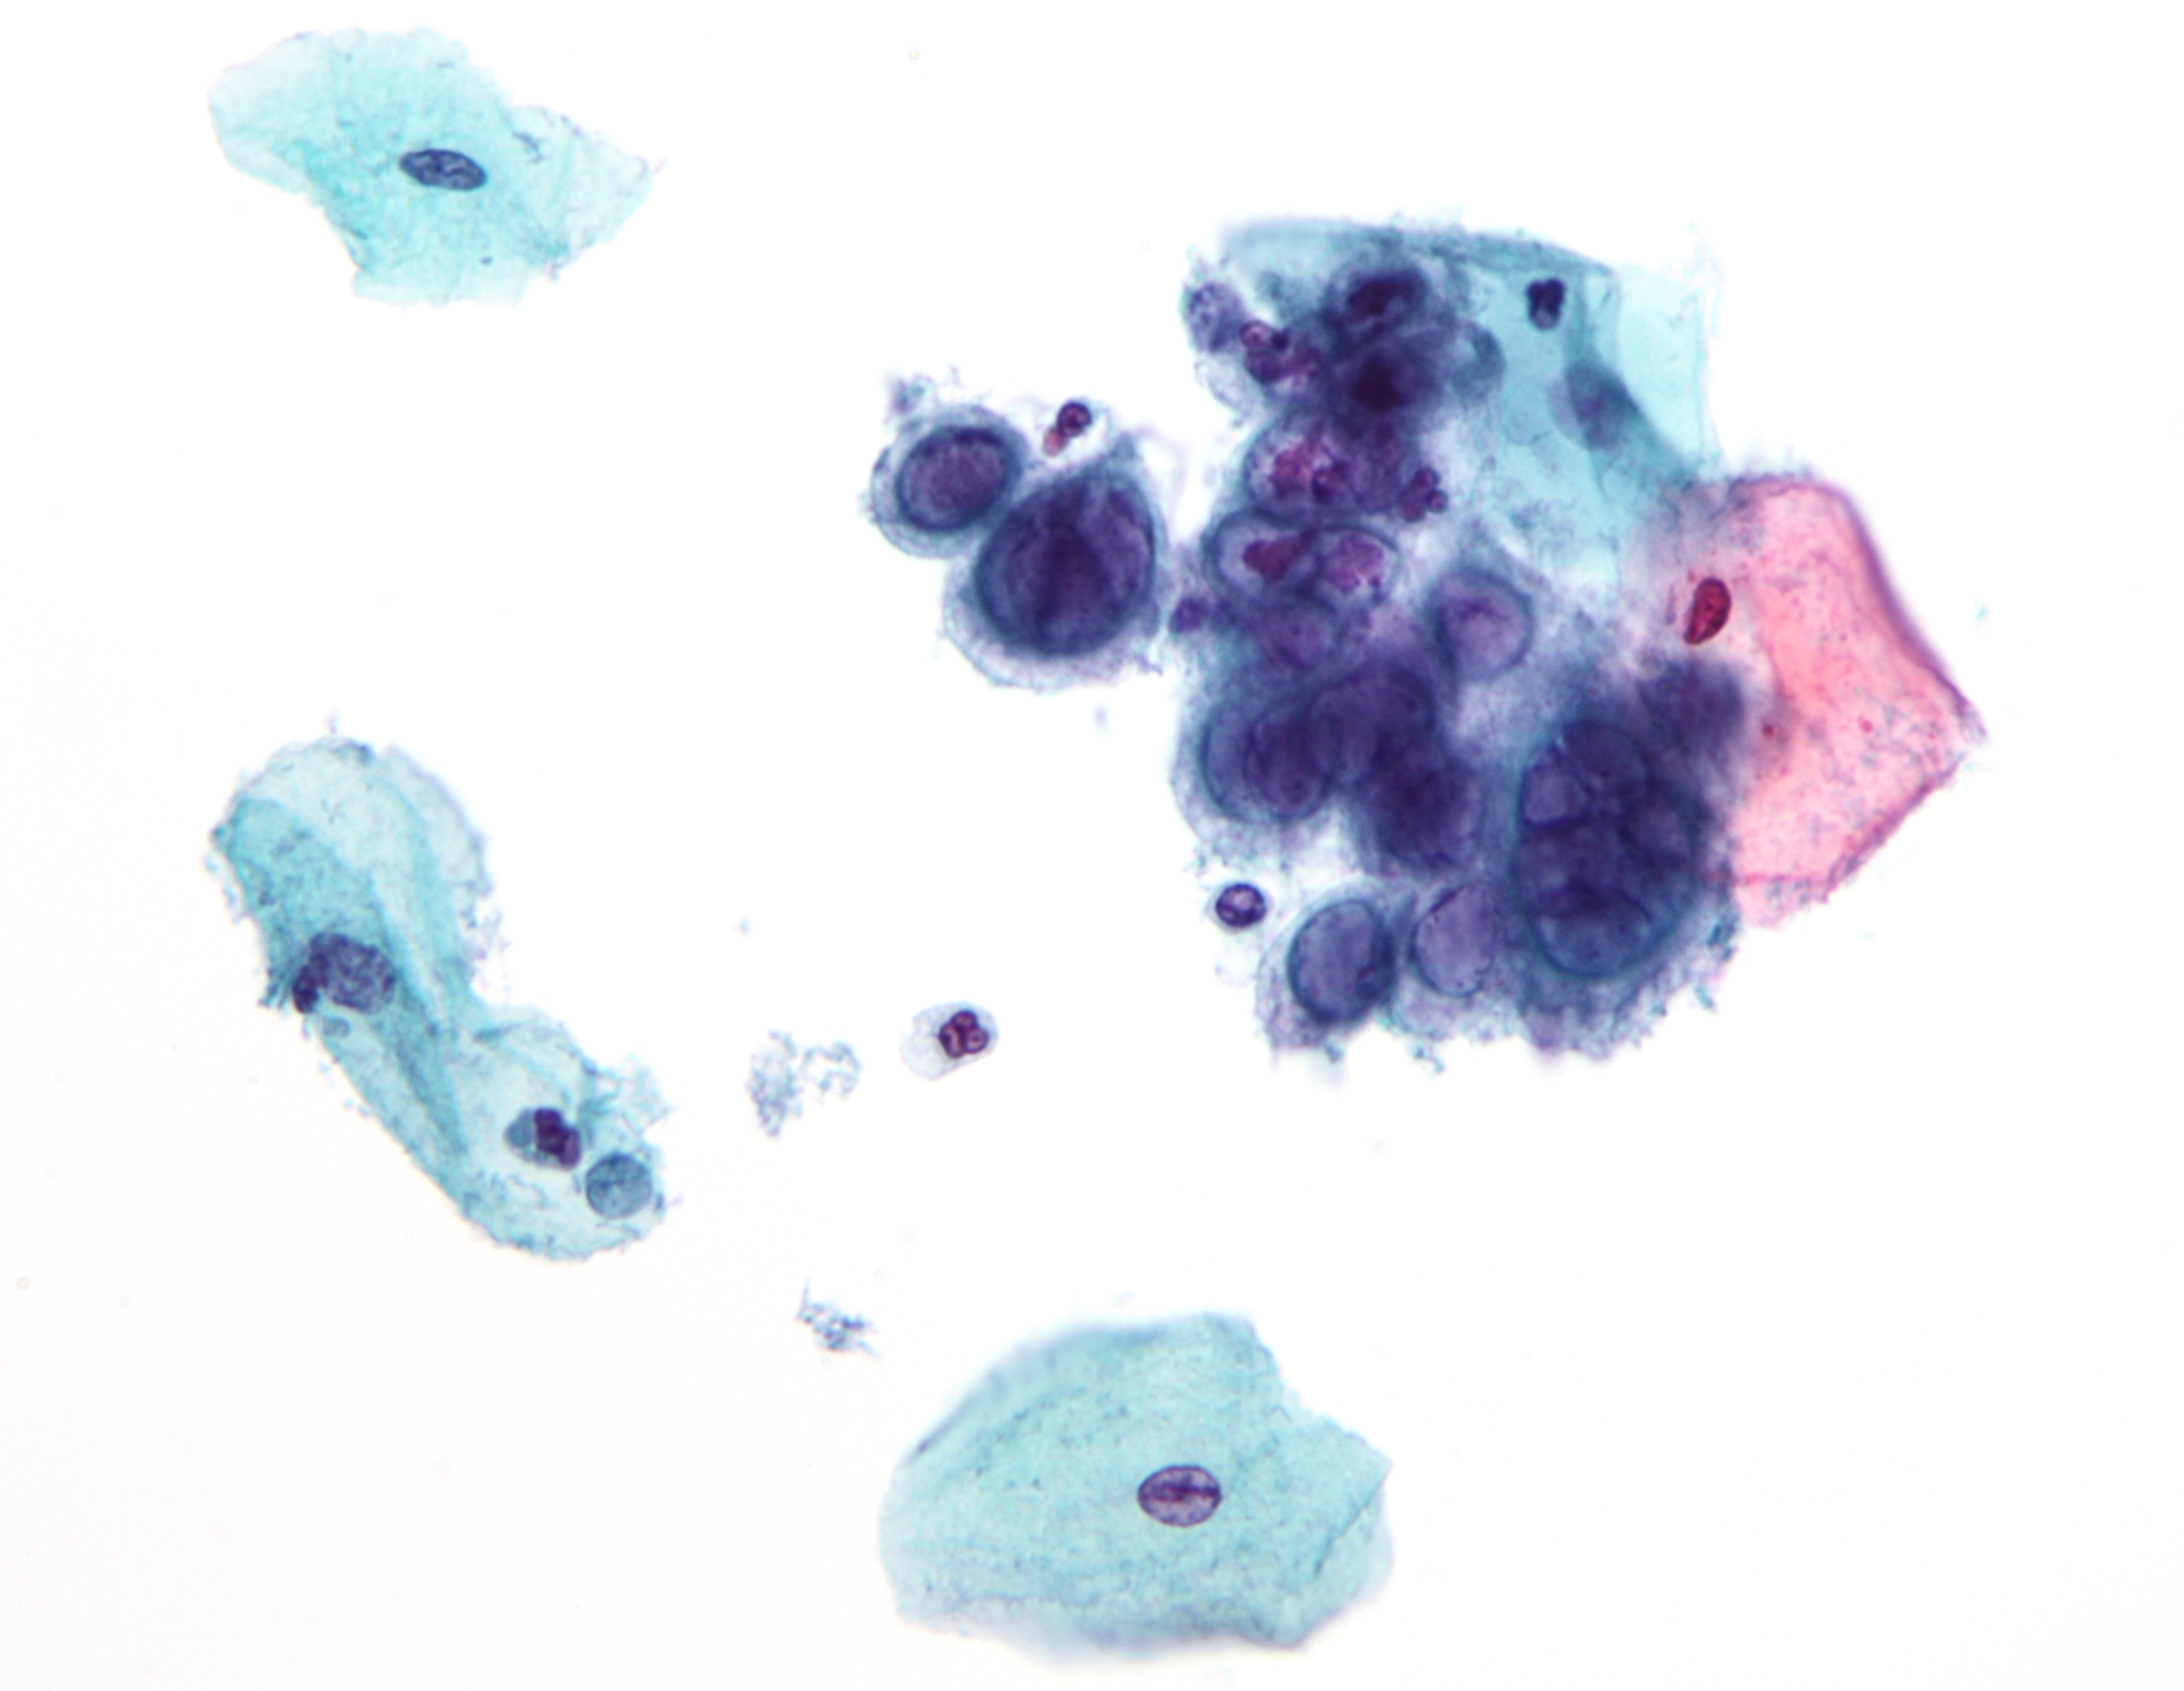

자궁경부암은 인유두종바이러스 감염이 주원인인 자궁 경부의 악성 종양으로, 초기에는 증상이 미미하지만 진행 시 질 분비물 증가, 성교통, 골반통이 나타날 수 있으며, 자궁경부 세포진 검사, 조직 생검 등으로 진단하고 수술, 방사선 치료, 항암 치료 등으로 치료하며, HPV 백신 접종과 정기 검진으로 예방이 가능하다. - 성병 - 매독

- 인유두종 바이러스(HPV): 미국에서 가장 흔한 성병으로,[230] 40가지 이상의 종류가 있으며, 대부분 건강 문제를 일으키지 않지만, 일부는 생식기 사마귀나 자궁경부암 등을 유발할 수 있다. 90%의 경우 2년 이내에 자연적으로 감염이 제거된다.[231] 생식기 접촉이나 구강 성교를 통해 전염될 수 있으며, 감염된 파트너는 증상이 없을 수 있다.

- 인유두종 바이러스(HPV): 피부 및 점막 접촉으로 발생하며, 고위험 유형의 HPV는 거의 모든 자궁경부암과 일부 항문암, 음경암, 외음부암을 유발한다.[220] 일부 다른 유형의 HPV는 생식기 사마귀를 유발한다.